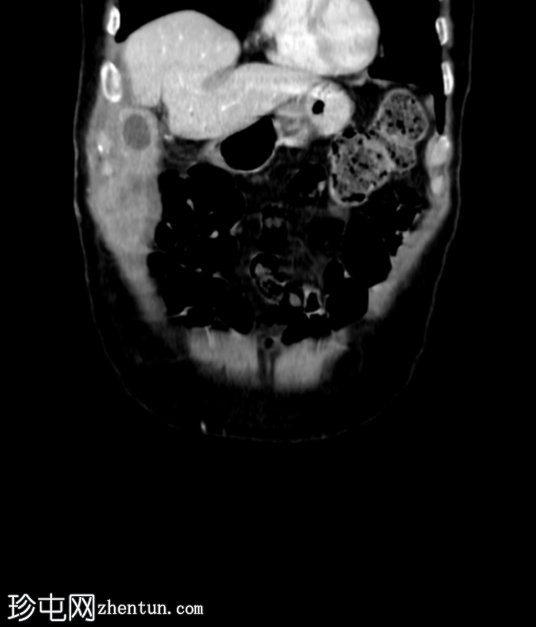

冠状位增强扫描

门静脉期

胆囊底部可见一枚较大的(3厘米)高密度结石,胆囊壁增厚并强化,主要位于胆囊底部。胆囊壁可见一小穿孔,感染扩散至胆囊外,并在肝下区可见气体腔。感染进一步扩散至腹壁肌肉,腹壁肌肉内可见脓肿,边缘强化明显,囊性坏死中心,腔内可见气体腔。十二指肠第一段与炎症胆囊粘连。

检查结果提示急性胆囊炎合并腹壁脓肿。

右侧膀胱有两个小憩室。